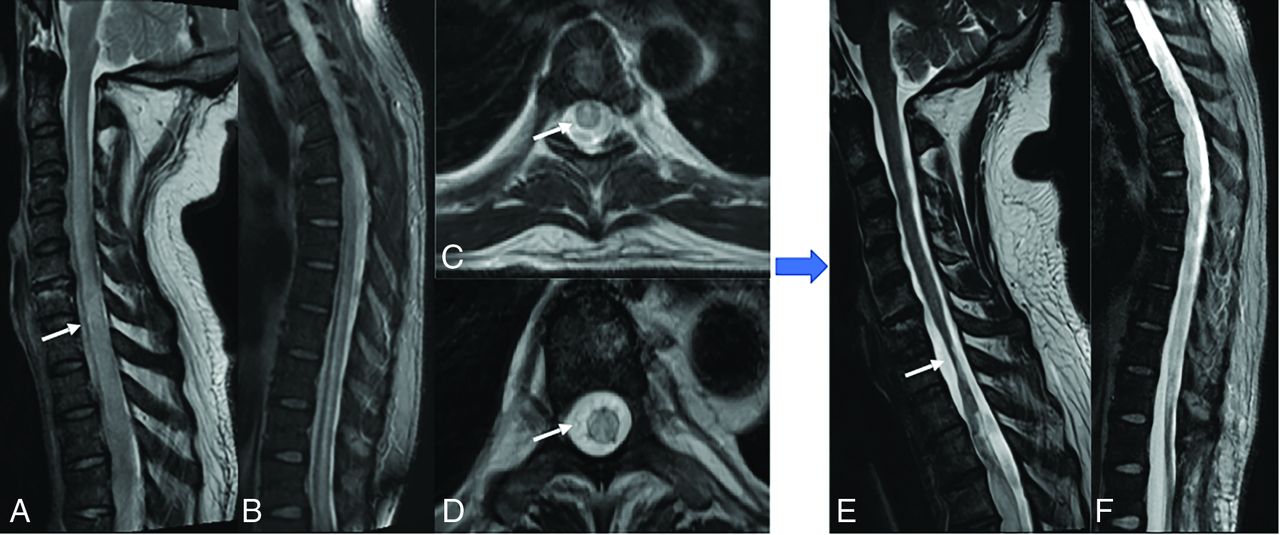

ATM is generally idiopathic or postinfectious immune-mediated demyelination, with EBV being a rare culprit.4,37,38 EBV myelitis is characterized by T2 hyperintensity in the spinal cord that extends over ≥2 segments covering equal or more than two-thirds of the cord, with the thoracic cord being the most affected (Figs 2 and 3). Enhancement patterns range from none to diffuse, with leptomeningeal and nerve root enhancement reported.37,39,40 EBV serologies can aid in diagnosing postinfectious EBV myelitis/ATM because MR imaging findings resemble those of other ATM etiologies. Spinal cord ischemia, MS, neuromyelitis optica, and autoimmune-related myelitis are imaging differential diagnoses for ATM. MS plaques usually affect less than one-half of the cord area and may have concomitant brain lesions. Spinal cord infarction shows bilateral anterior horn cell T2 hyperintensity symmetrically.38 Although rare in immunocompetent individuals, EBV ATM should be considered in cases of high CSF cell count atypical for idiopathic ATM.40

Presumed EBV myelitis, CSF EBV-positive. Conus biopsy revealed fibrin with macrophages, scant peripheral nerve myelins, and degenerating myelin, most consistent with infection. T2-weighted sagittal image of the cervical (A) and thoracic (B) spine along with axial images (C and D) reveal diffuse long-segmental T2-hyperintense signal in the spinal cord (arrows). Eight-month follow-up sagittal T2 (E and F) images show cord atrophy with persistent signal abnormality (arrow).